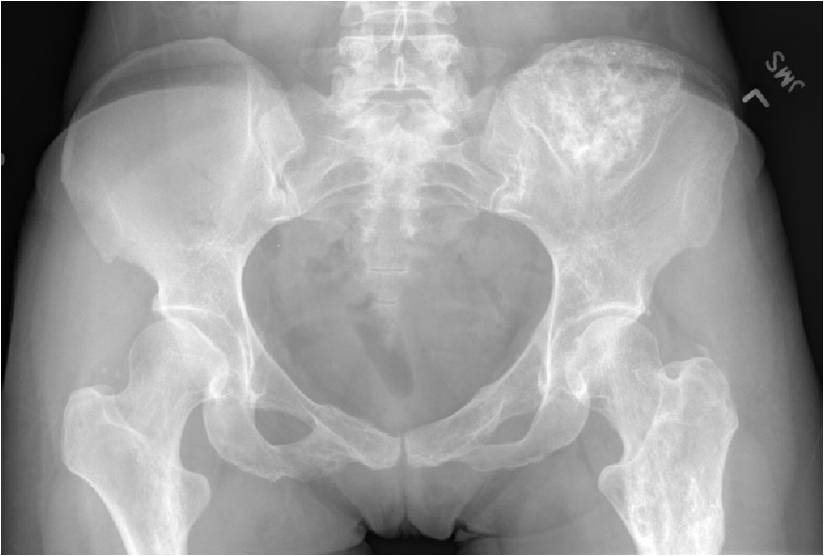

- Enchondromas of the pelvis, vertebrae and ribs are uncommon

- Almost all hyaline cartilage tumors of the pelvis are considered malignant based on anatomic location no matter what the pathology shows. These tumors will ultimately grow locally and have the potential to dedifferentiate or change into a higher grade chondrosarcoma.

Metaphyseal Tumor, Heavy Calcifications, Ring and Arc Pattern of Calcifications, Minimal Endosteal Scalloping, No Cortical Destruction, No Periosteal Reaction, No Cortical Destruction, No Soft Tissue Component

Metaphyseal Tumor, Heavy Calcifications, Ring and Arc Pattern of Calcifications, Minimal Endosteal Scalloping, No Cortical Destruction, No Periosteal Reaction, No Soft Tissue Component